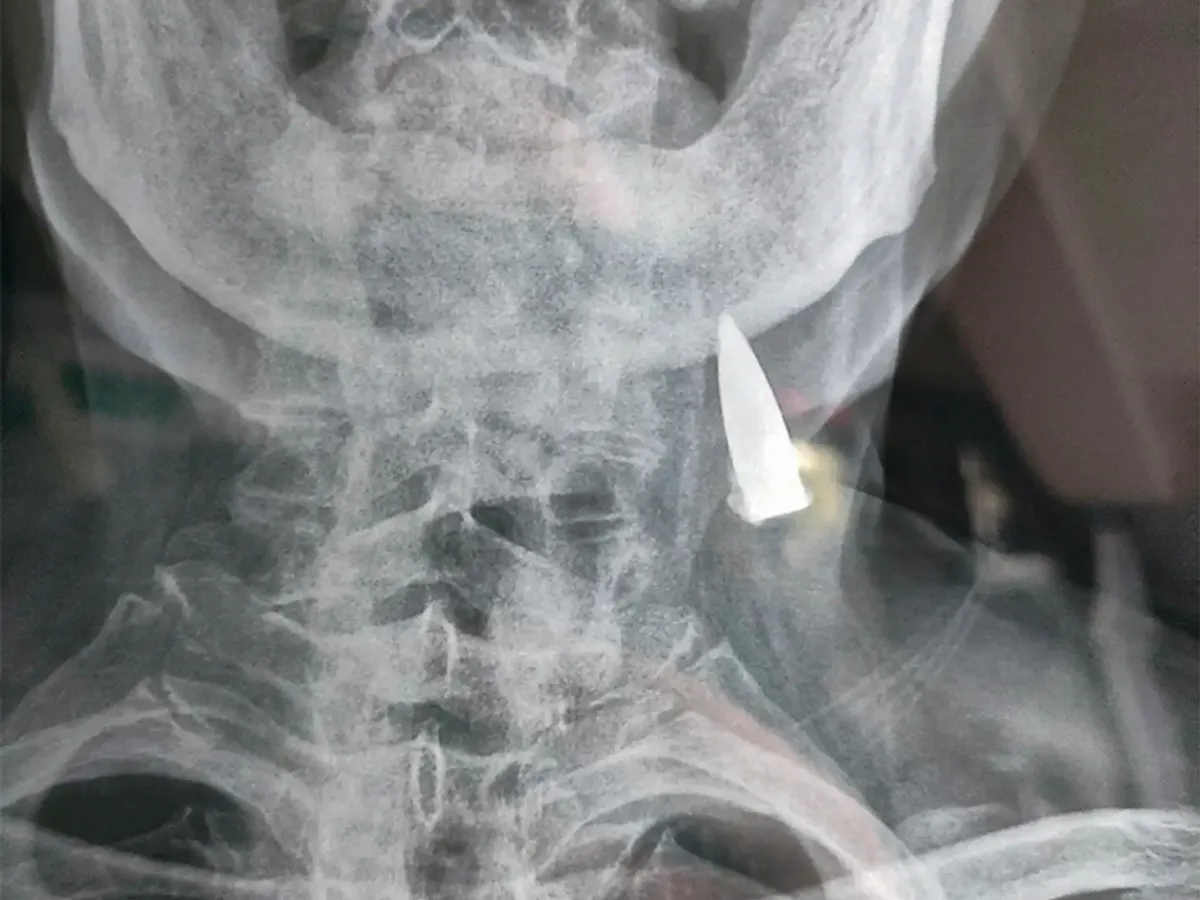

FOTO Un veteran a trăit 77 de ani cu un glonț în gât. În 1945 a fost împușcat și nu a știut până azi

Medicii care au efectuat o radiografie au fost uimiți să descopere un glonț înfipt în gâtul unui veteran al armatei la aproape 80 de ani după ce acesta a suferit rana - și nici măcar nu și-a dat seama că se afla acolo.

Radiografia unui fost soldat a dezvăluit o surpriză șocantă, când s-a dovedit că un glonț se afla încă în gâtul său după 80 de ani.

Zhao He, în vârstă de 95 de ani, avea glonțul înfipt în corp încă din timpul celui de-al Doilea Război Mondial, dar nici măcar nu a știut că se afla acolo până când personalul medical de la un spital din Shandong, China, a descoperit obiectul vechi de zeci de ani.

În mod miraculos, experții medicali spun că glonțul nu i-a provocat nicio problemă lui Zhao - în ciuda faptului că a rămas înfipt în gât timp de 77 de ani.

Din această cauză și din cauza vârstei lui Zhao, glonțul nu va fi îndepărtat, deoarece scoaterea lui ar implica o operație riscantă.